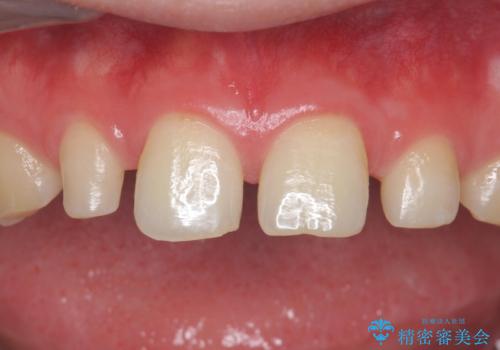

矯正治療とかぶせ物での治療どちらともご提案したところ、かぶせ物での治療をご希望されたためクラウンでの審美性回復を試みることとなりました。

形のイメージを反映させた仮歯を調整し、技工士さんと連携して製作したため口元に調和した非常に審美的なクラウンを装着することができました。